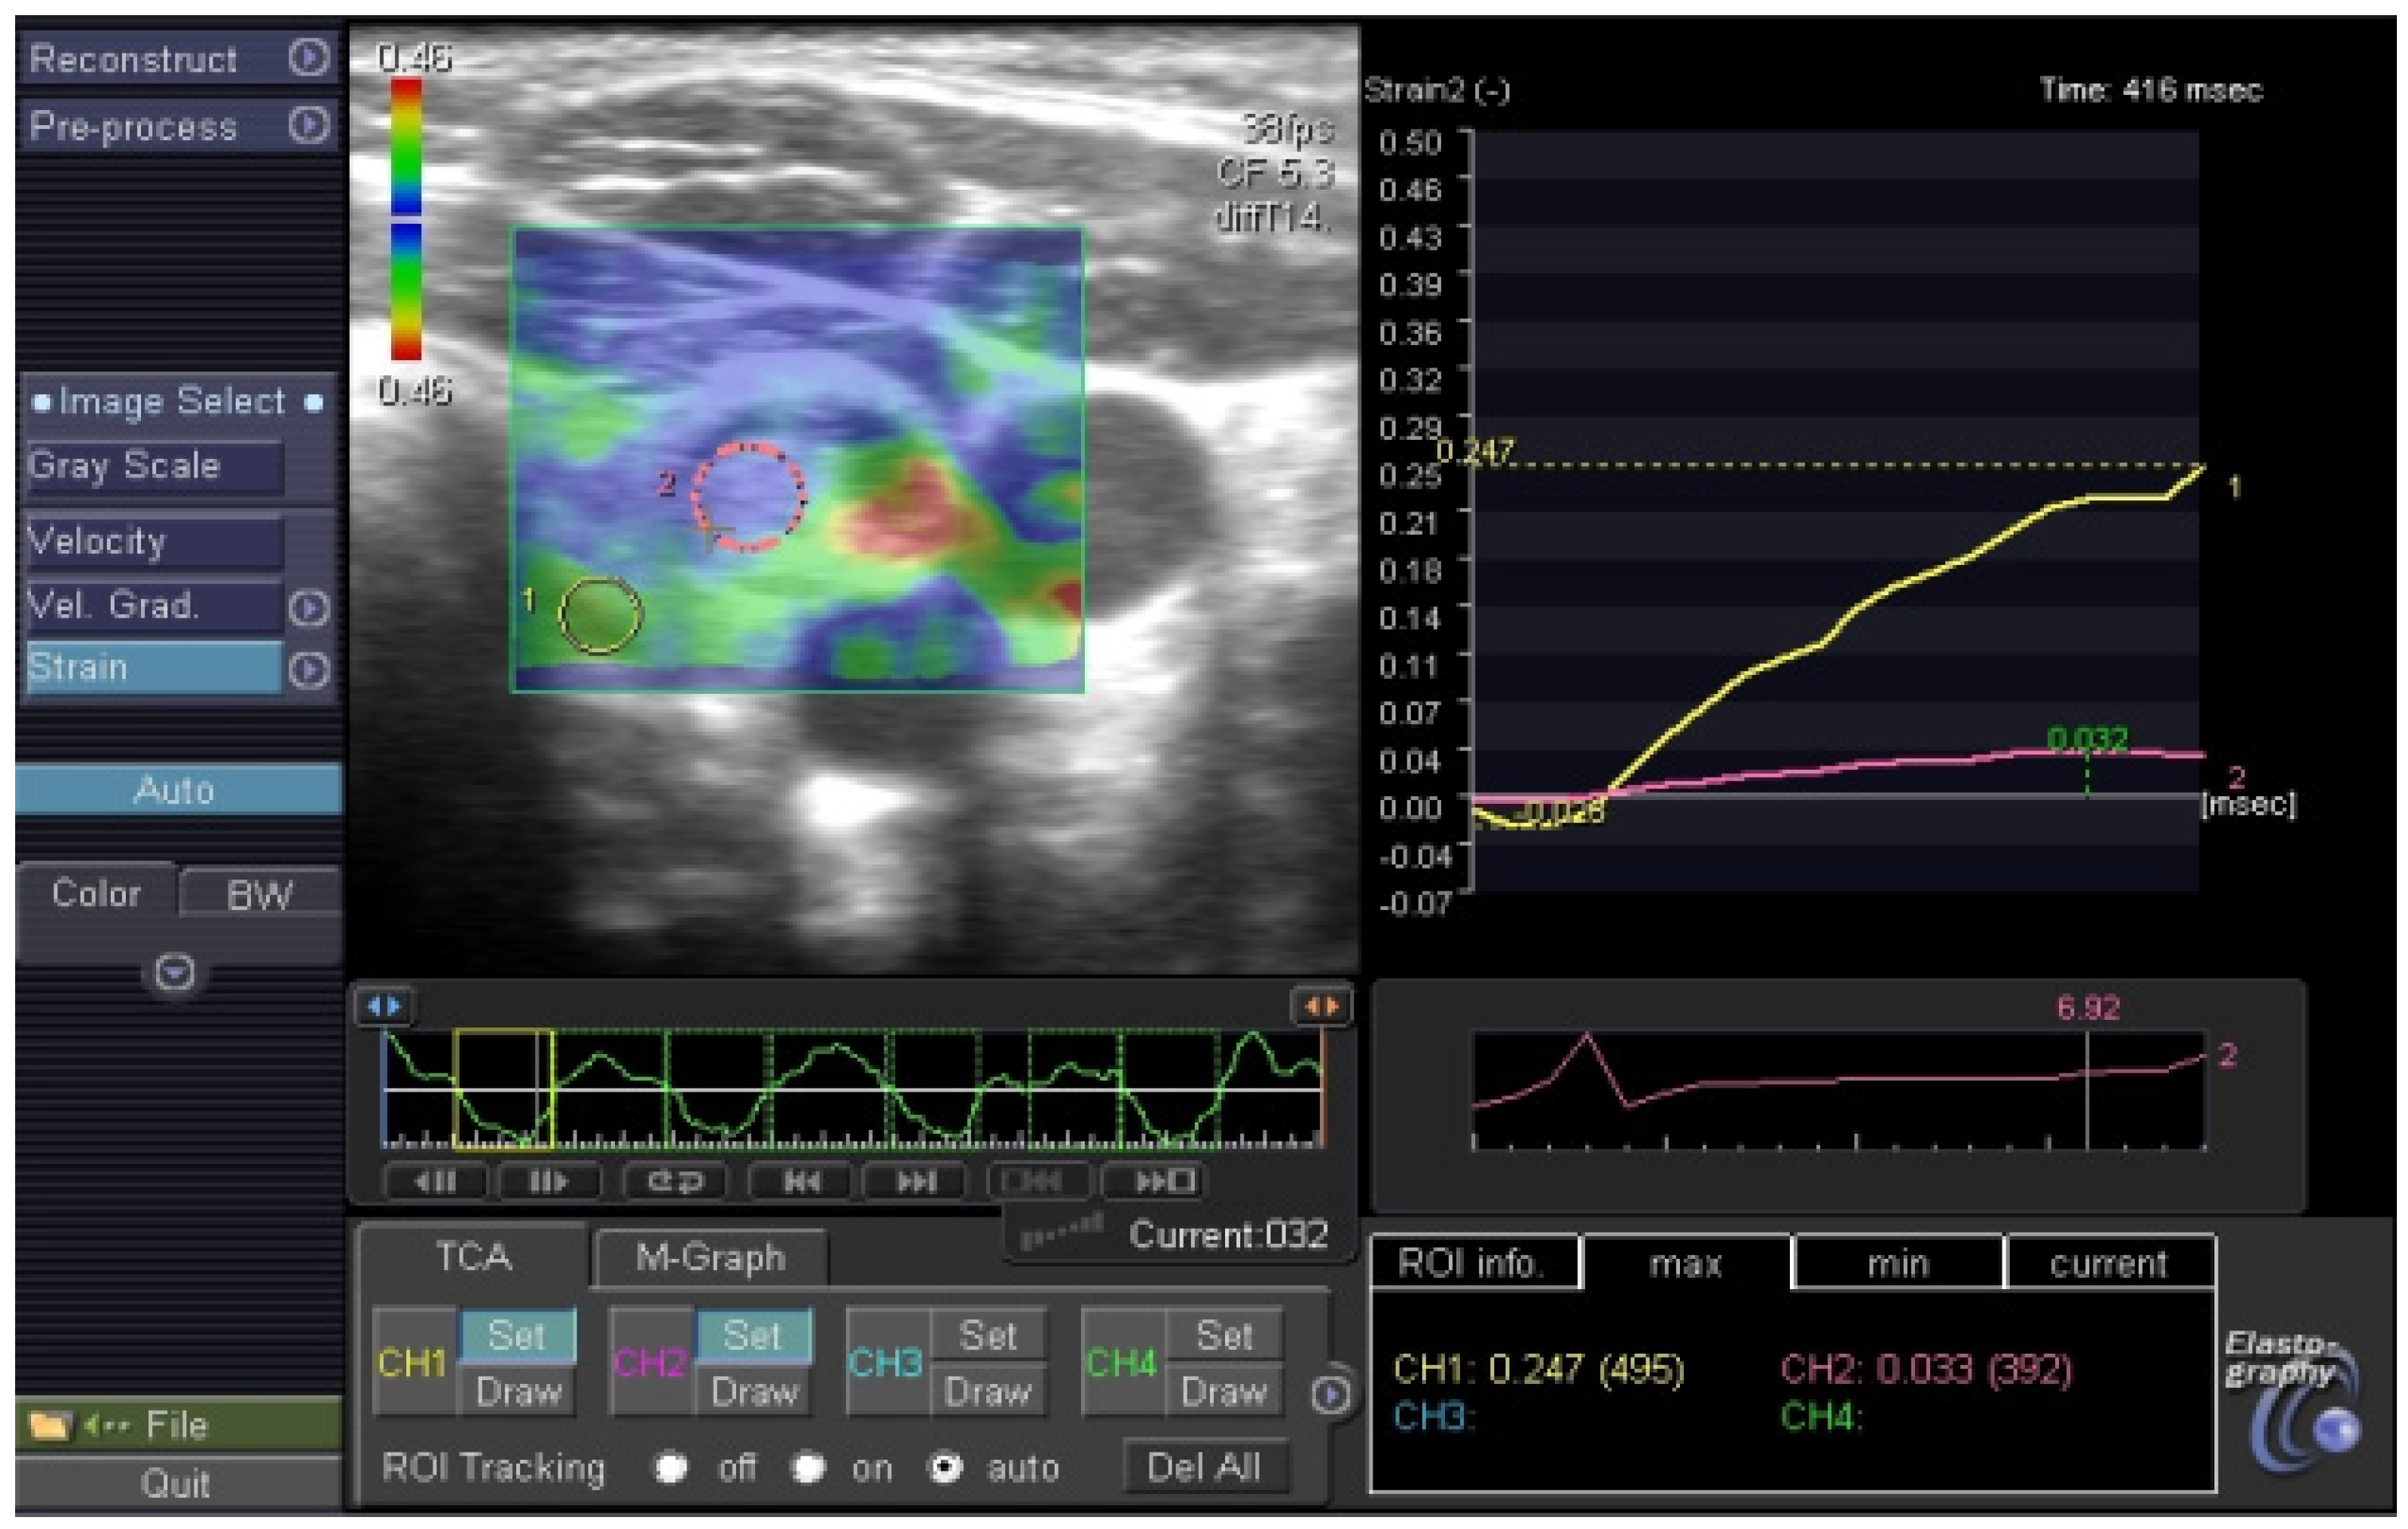

2.3. Thyroid Ultrasonography, Elastography and Fine Needle Aspiration Biopsy

3.1. Elastography